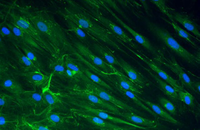

- Confirmation of the nature of differentiated cells by ICC method

- Investigation of cell placement on tissue scaffold